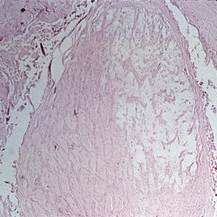

Slide 12-26

Feb 27 2019 by Lancaster Course in Ophthalmology

Sequelae. Massive peripheral anterior synechia and ectropion uveae have resulted from blunt trauma. Note the postcontusion deformity of the anterior chamber angle (H&E x40).

Condition/keywords: anterior synechiae, ectropion uveae, sequelae